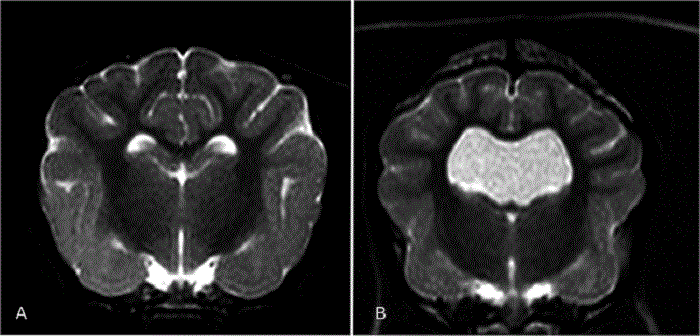

Below is a comparison between a canine brain with normal lateral cerebral ventricles (A) and one with enlarged lateral ventricles (B). From a May 2015 study led by Dr. Martin J. Schmidt.

More advanced imaging, computed tomography (CT) and especially magnetic resonance imaging (MRI), is necessary to fully determine the extent of the ventriculomegaly or hydrocephalus, to identify obstructive lesions, and to rule out other disorders. MRI is more sensitive than CT in diagnosing these disorders. However, CT is useful for follow-up of previously diagnosed patients. (See below, the MRI images comparing normal dogs with dogs diagnosed with ventriculomegaly and hydrocephalus. From Laubner 2015.)